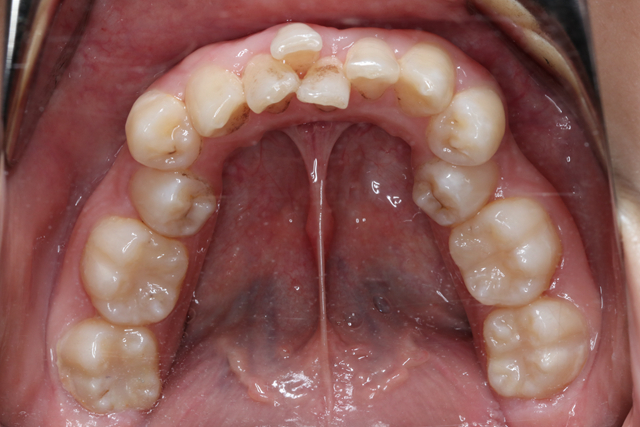

02 牙齿拥挤

恒牙萌出早期轻度拥挤,随着后牙生长和萌出颌骨的骨量随之增大可自行调整;

中度拥挤的患儿,需要全面评估,决定是否早期矫治;

重度拥挤的患儿往往在替牙结束后需要接受拔牙矫治。

但是如果因为牙齿拥挤导致个别牙齿反合、咬合创伤应及时干预治疗,否则对儿童牙齿健康、咬合功能、颜面发育都会带来不利影响。